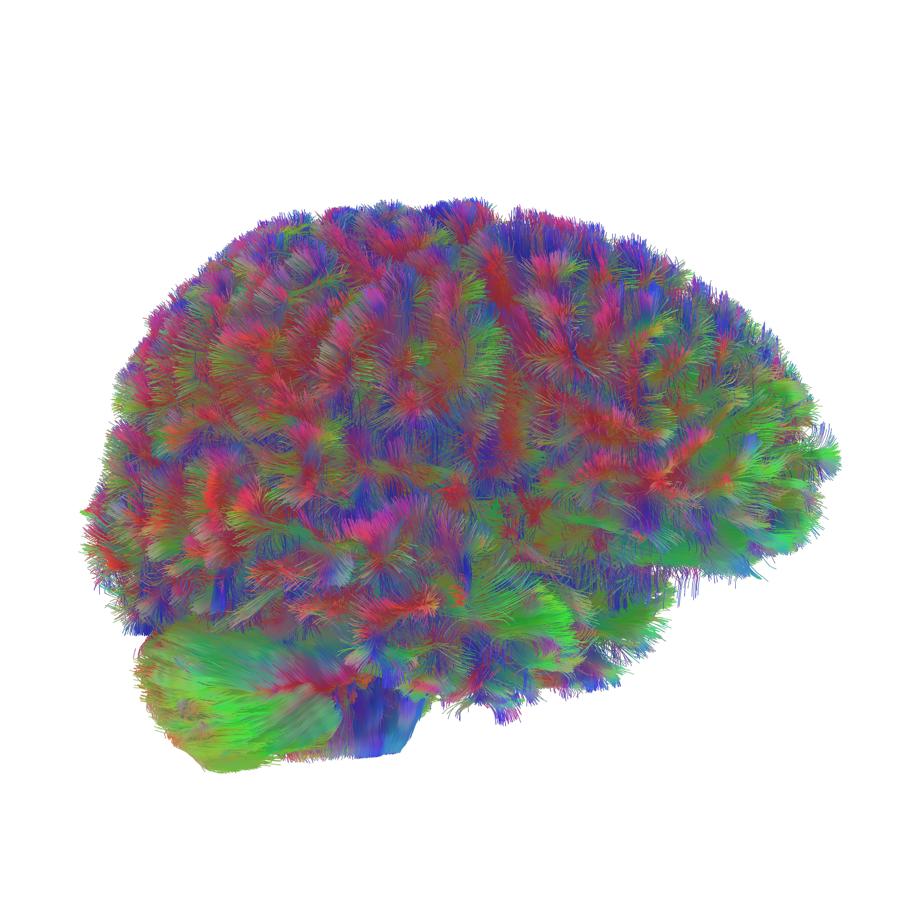

Las BCI son unas herramientas que, mediante sensores implantados en el cerebro, captan las señales eléctricas que las neuronas usan para transferir información por todo el cerebro y las convierten en acciones.